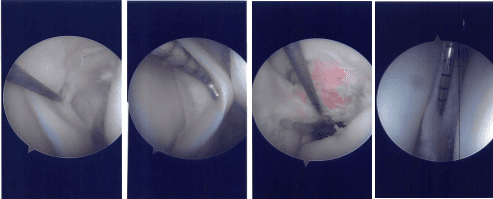

Esmarch was applied and the tourniquet was inflated to 300 mmHg. Patellofemoral joint was found to be in good shape with no cartilage damage. The scope was taken to the medial gutter where there was a synovial flap. Medial compartment showed a ramp lesion of the posterior body of the medial meniscus.

Probe was inserted and meniscus tear was again checked. It involved the posterior body of the medial meniscus along the capsule. The decision was made to repair the ramp lesion using all-inside suture configuration using FasT-Fix.

Two curved and two reverse curved FasT-Fixes were used to complete the repair after the meniscus was abraded along with a capsule abrasion done with the shaver. The repair was found to be in good position.

Intraoperative Arthroscopy Images

Now the scope was moved to the internal trochlear area where ACL was deficient. Debridement was done. The scope was moved to the lateral compartment where we found medial edge fraying as well as a small bucket handle tear of the medial edge of the lateral meniscus.

Further examination showed a horizontal tear going up to the periphery of the lateral meniscus of the posterior body. Three FasT-Fixes were used for repair of the lateral meniscus, horizontal lesion.

Before that, posterolateral incision was given anterior to the fibula. With sharp and blunt dissection making a plane behind the LCL and between the knee capsule in the lateral head of gastrocnemius, a plane was made.

Sims speculum was inserted to protect the posterior neurovascular bundles. After it was done, the scope was reentered and the repair of the left meniscus using FasT-Fixes were done in a satisfactory fashion. Microfracture of the trochlear notch was performed using bundle fix.